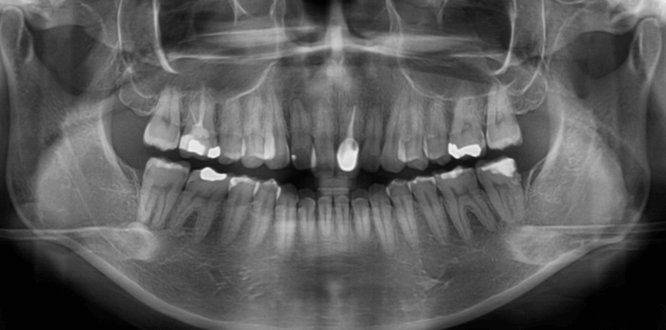

咬み合わせが逆であること(反対咬合)が気になる

| 年齢・性別 | 15歳 女性 |

|---|---|

| 主訴 | 咬み合わせが逆であること(反対咬合)を気にされて来院された女性。見た目や機能面の改善を希望されていました。 |

| 治療期間・回数 | 4年4ヶ月・28回 |

| 費用 | 900,000円 |